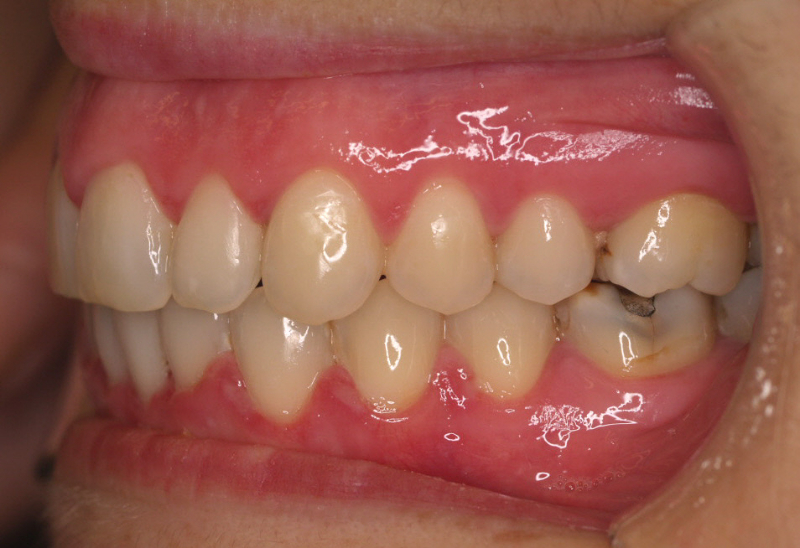

Premolar mandibular incluido + fenestración

45 incluido